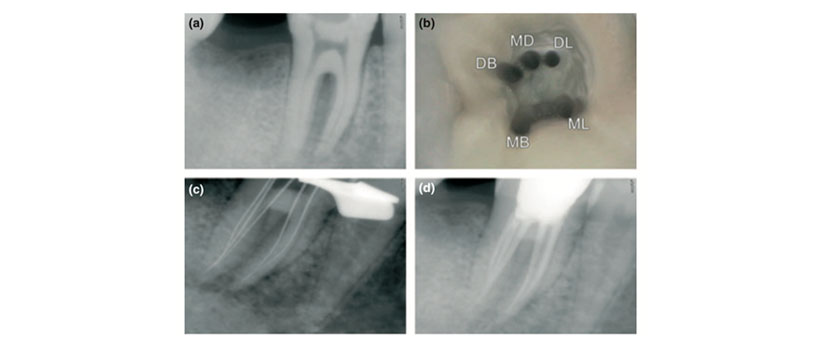

Figura 1: a) Radiografía preoperatoria del diente 46. (b) Abertura de acceso que muestra cinco canales (MB, Mesiobuccal; ML, Mesiolingual; DB, Distobuccal; MD, Distal medio; DL, Distolingual). (c) Radiografía de longitud de trabajo del diente 46 en angulación excéntrica. (d) Radiografía post-obturación del diente 46.